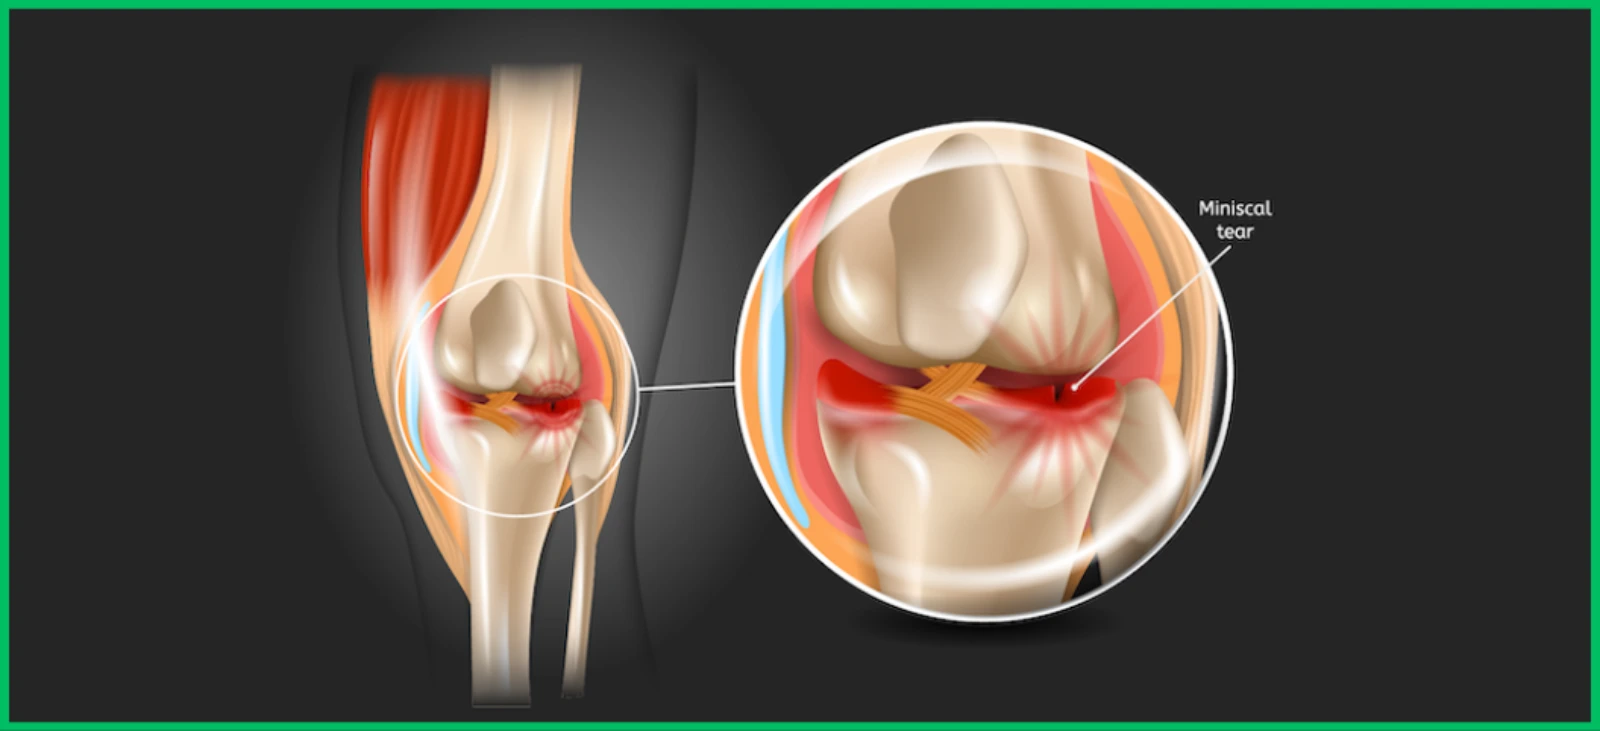

Sports Testing for Injury Prevention: What Bangalore Athletes Need to Know Injuries can derail the training and careers of athletes if not prevented through targeted strategies. Sports testing is emerging